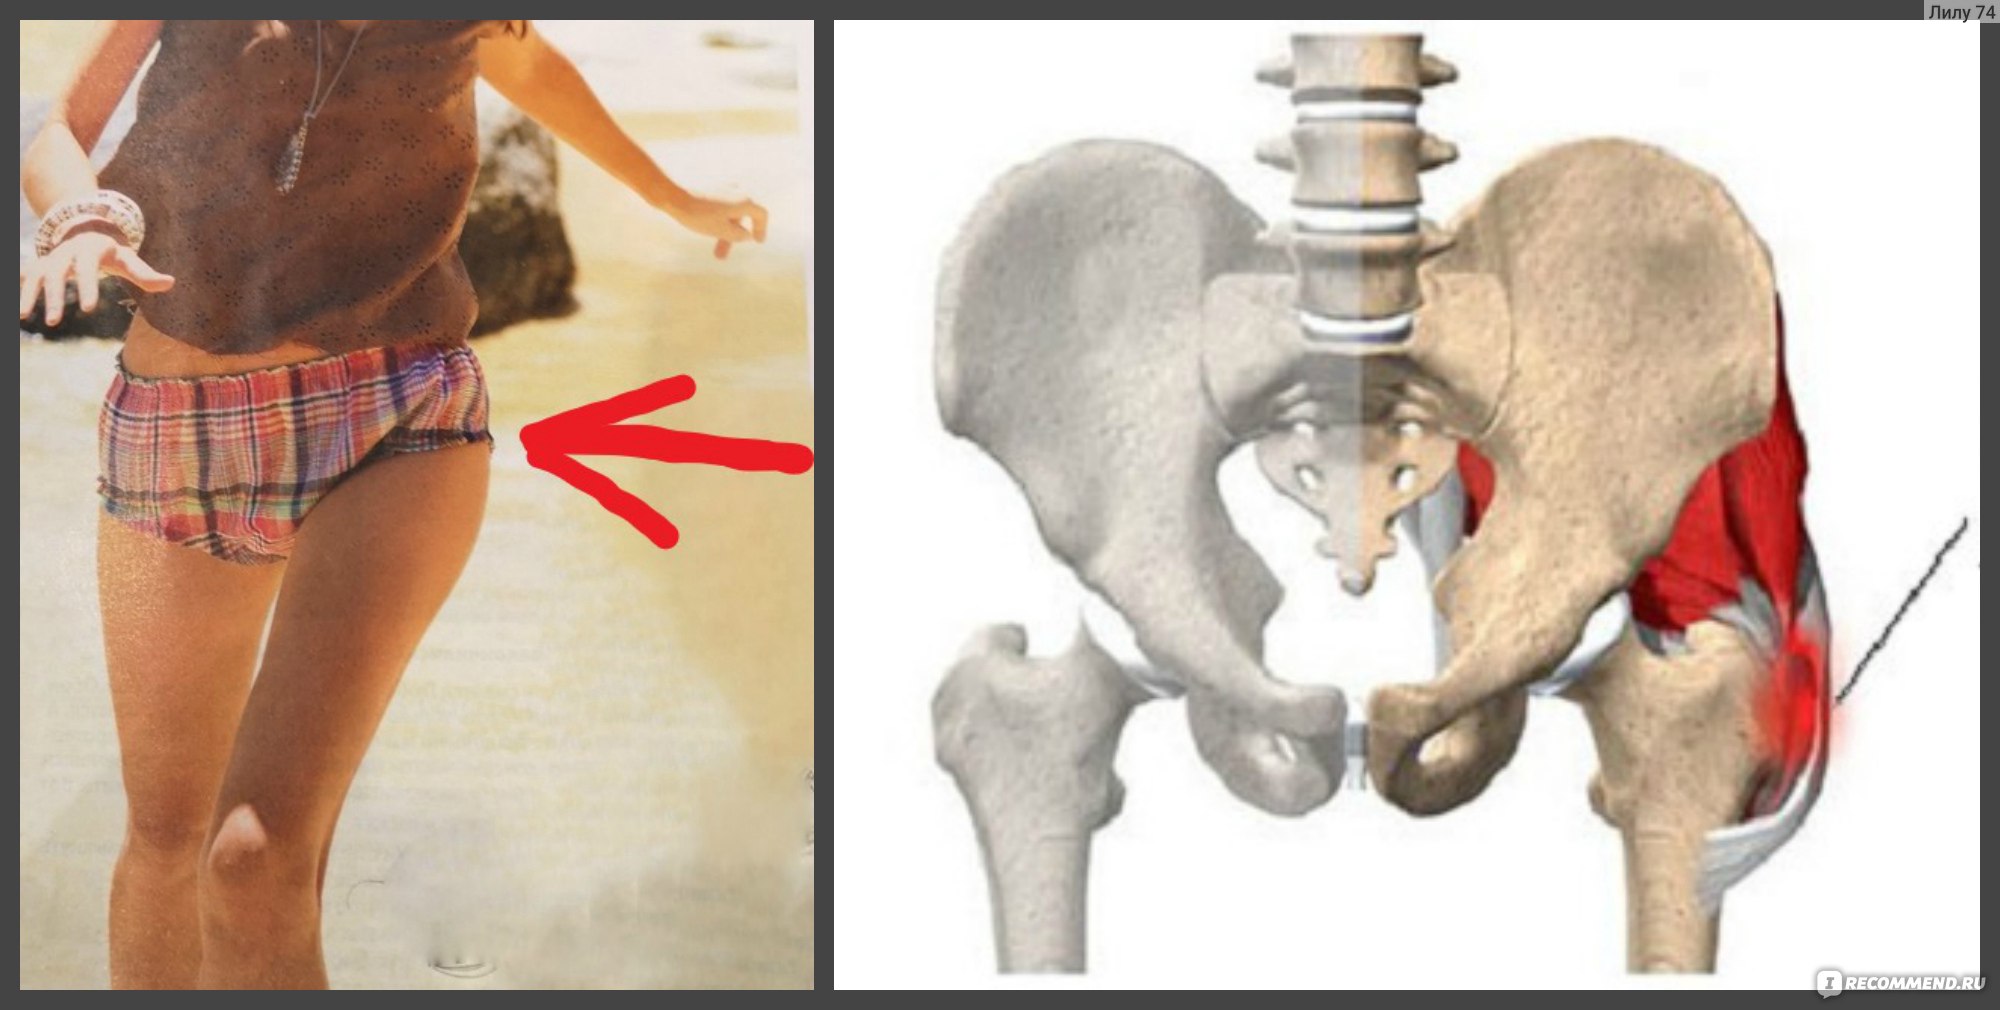

Здоровье суставов: Трохантерит и его влияние на мышцы